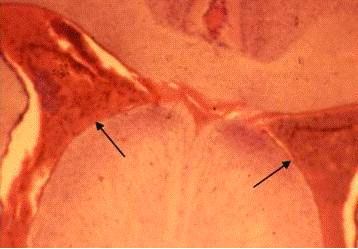

Моделирование последствий удаления невриномы VIII нерва заставляет нас обратить особое внимание на комплекс вестибулярных ядер, от которого начинается еще одна нисходящая система: вестибулоспинальный тракт. В этот комплекс входят следующие ядра: верхнее (Бехтерева), медиальное (Швальбе), нижнее (нисходящее), латеральное (Дейтерса) и группа x, y, z (Бродал с соавт., 1966). Нисходящий вестибулоспинальной тракт берет начало из латерального вестибулярного ядра (Дейтерса). Последнее имеет более тесные, чем другие вестибулярные ядра, связи со спинным мозгом. Окончания вестибулоспинальных нейронов обнаруживаются на интернейронах и мотонейронах VII-VIII пластин серого вещества спинного мозга. Следует отметить соматотопическую организацию вестибулоспинальной проекции. Повреждение ствола на уровне ядра Дейтерса с одной стороны приводит к нарушению позы животного. Это обусловлено нарушением взаимодействия мышц сгибателей и разгибателей, находящихся под контролем вестибулоспинального тракта (Бродал с соавт., 1966; Bacskai et al., 2002).